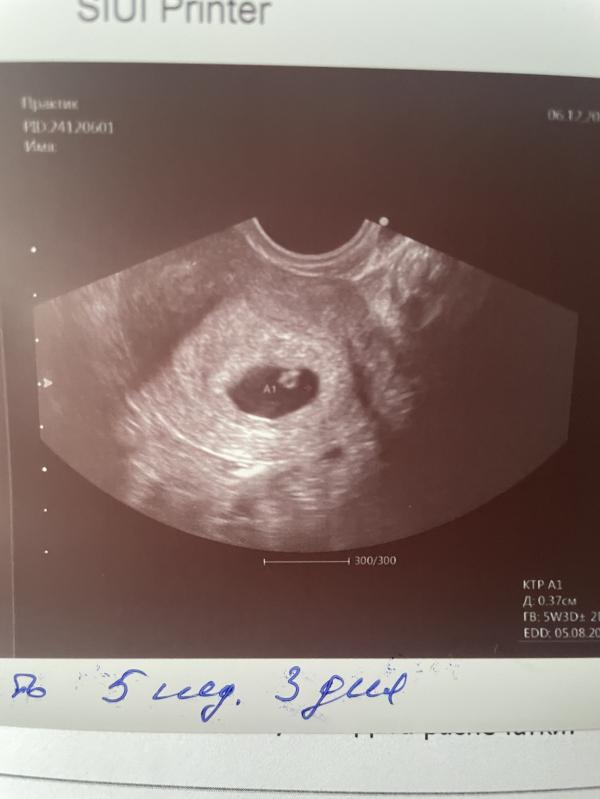

Можно считать начало второй беременности открытым 😃🤰🏻♥️

Сходила на узи, 5.3 недель поставили. ♥️ -144 удара